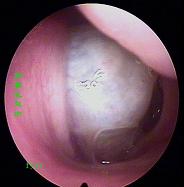

鼻炎长期得不到有效治疗导致鼻息肉以及鼻腔囊肿